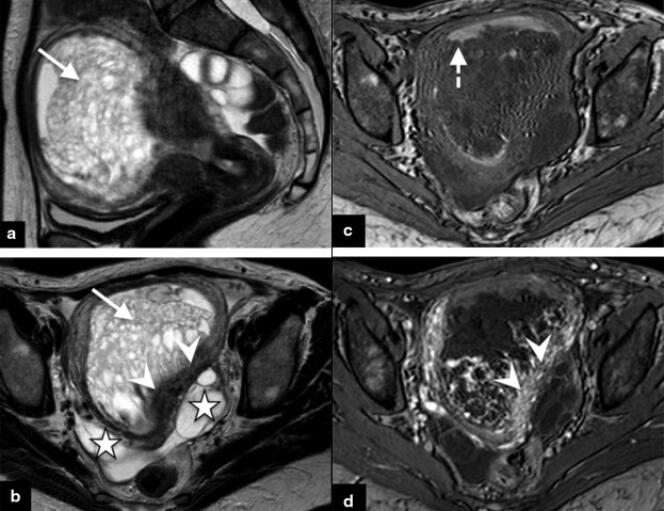

IRM pelvienne mettant en évidence une môle invasive chez une patiente de 40 ans présentant des hémorragies de l’utérus. PIERRE-ADRIEN BOLZE Ce sont des tumeurs féminines méconnues,d’autant plus cruelles qu’elles surviennent à l’occasion de l’attente d’un « heureux événement ». Chez près d’une femme enceinte sur mille en Occident (et près d’une sur cent en Asie),en effet,une masse tumorale se développe à partir du placenta,cet organe essentiel qui assure les échanges entre le sang de la mère et celui de l’embryon.

Lors de ces grossesses pathologiques,des lésions précancéreuses,nommées « môles hydatiformes »,se développent à partir d’une couche de cellules,le trophoblaste,qui,en temps normal,entoure l’embryon et forme de nombreuses villosités qui ancrent le placenta dans l’utérus.

Il arrive que ces môles provoquent une fausse couche spontanée, mais,souvent,sans expulser la totalité de la masse tumorale. La femme présente alors des saignements persistants qui l’incitent à consulter. Après échographie et aspiration,le diagnostic est confirmé par l’analyse histologique des tissus évacués.